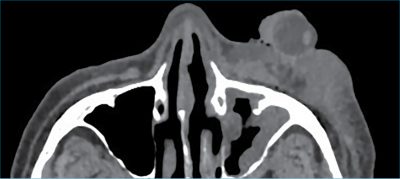

Ezen szövetek előtt, extrakorporálisan ábrázolódik az alakját megtartott bulbus, amely irányának meghatározásában segítséget nyújtott a jól ábrázolódó, helyén levő hiperdenz lencse (4. ábra).